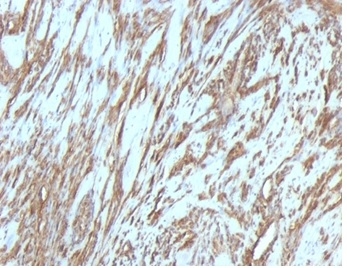

Formalin-fixed, paraffin-embedded human Leiomyosarcoma stained with Muscle Specific Actin Mouse Monoclonal Antibody (MSA/953).

This antibody recognizes actin of skeletal, cardiac, and smooth muscle cells. It is not reactive with other mesenchymal cells except for myoepithelium. Actin can be resolved on the basis of its isoelectric points into three distinctive components: alpha, beta, and gamma in order of increasing isoelectric point. Anti-muscle specific actin recognizes alpha and gamma isotypes of all muscle groups. Non-muscle cells such as vascular endothelial cells and connective tissues are non-reactive. Also, neoplastic cells of non-muscle-derived tissue such as carcinomas, melanomas, and lymphomas are negative.It stains tumors of smooth muscle (leiomyomas and leiomyosarcomas) as well as skeletal muscle (rhabdomyomas and rhabdomyosarcomas).